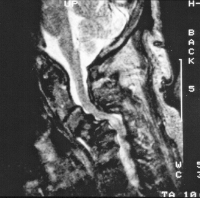

Abbildung 2: Sagittales T2-MRT mit Vertikalluxation des Dens.

Keywords: DensMRTVertikalluxation